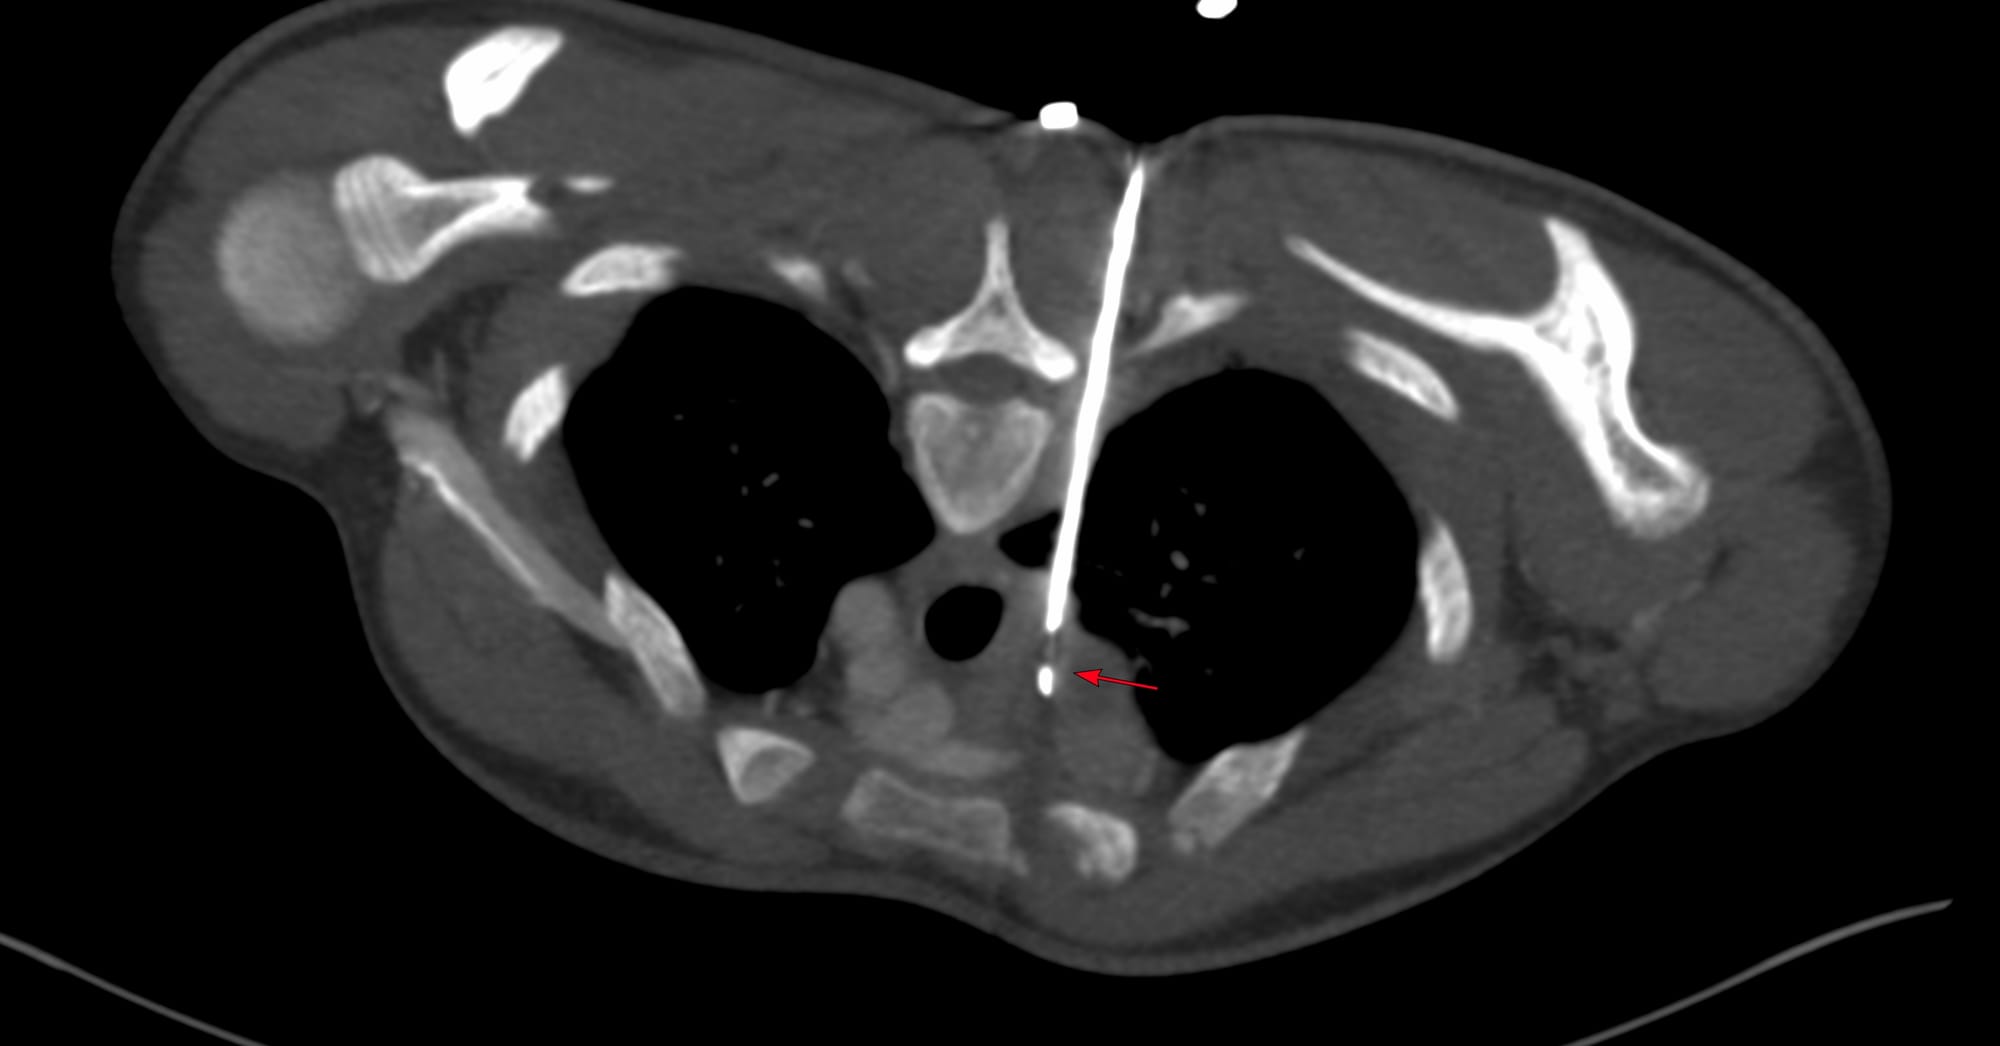

Case 172 - Right Adrenal Gland Biopsy Using an Ipsilateral Up Approach with Hydrodissection